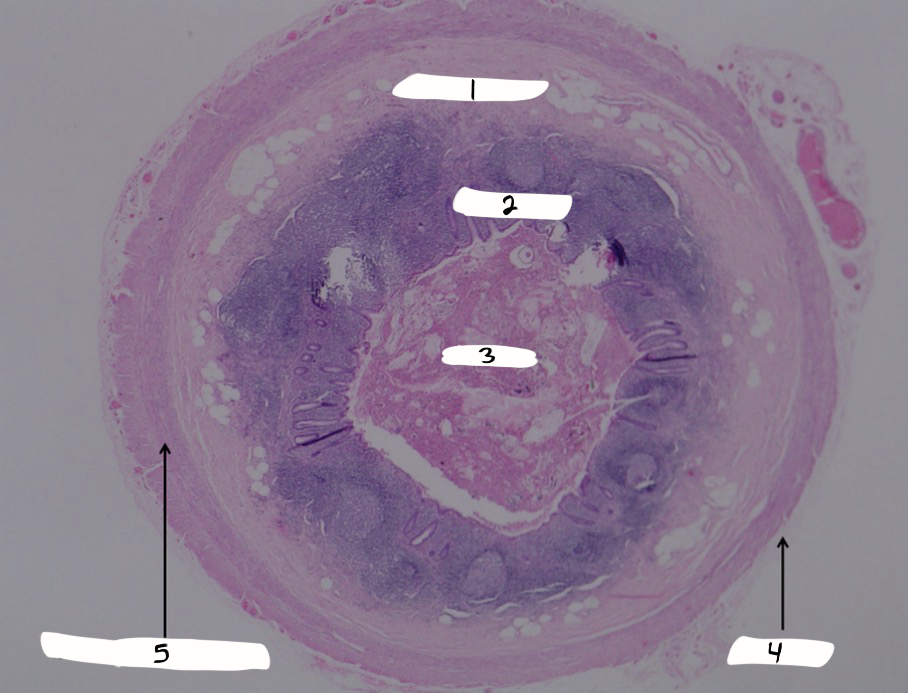

appendix

what is this a sample of?

submucosa

what is #1?

mucosa

what is #2?

lumen

what is #3?

serosa

what is #4?

muscularis externa

what is #5?